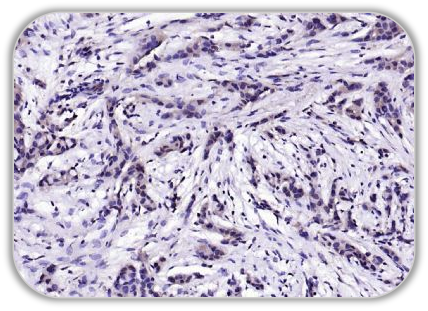

Anti-P63 antibody (bsm-33422M)

IHC Human Cervical Carcinoma